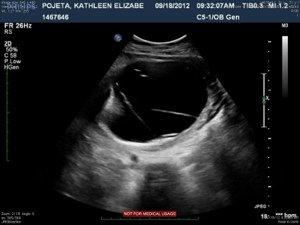

The next four images just show various views of the strands/septations that are visible within the sac.

20120921-213522.jpg